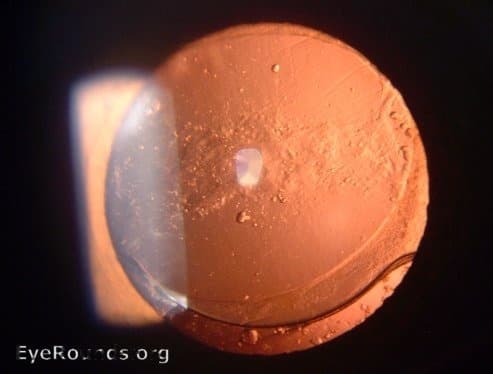

Clinical Images

High-resolution clinical photographs showing various presentations of cataracts.